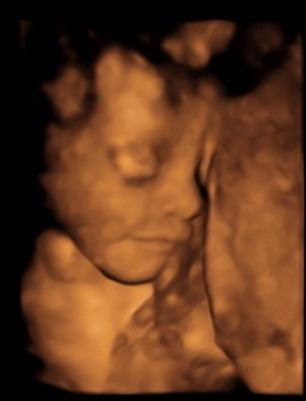

October ’15 – 4D scan of Noah

When we found out that the baby was a boy, the name books came out.

We finally chose Noah after many months of trialling other names.